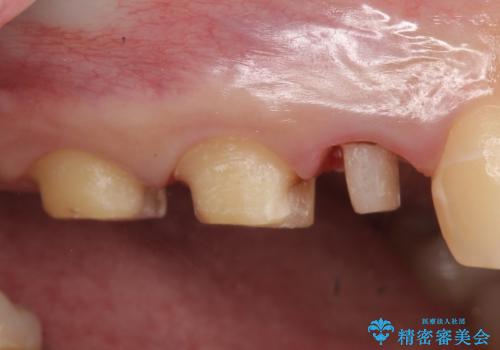

- 他院にて右上5番目の歯の根管治療を行っていたが、痛みが引かないため当院にいらっしゃった方の症例です。

右上5は再根管治療を行い症状の緩解を確認後、オールセラミッククラウンによる補綴を行いました。

右上6、7番目の歯もしみるとのことだったので古い樹脂及び虫歯を除去後、オールセラミッククラウンによる補綴を行いました。

※右上5は歯肉縁下まで虫歯だったため歯冠長延長術を提案しましたが、希望されませんでした。